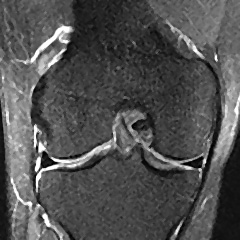

(left) This a normal knee seen from the front. (right) This knee has a severely torn menicus (note the missing black wedge - yellow arrow) and accompanying bone bruise (bright area in tibia - green arrow)

(left) This a normal knee seen from the side with an intact Anterior Cruciate Ligament (ACL) (yellow arrow). (right) One can also see the Posterior Cruciate Ligament (PCL) in this view (green arrow).